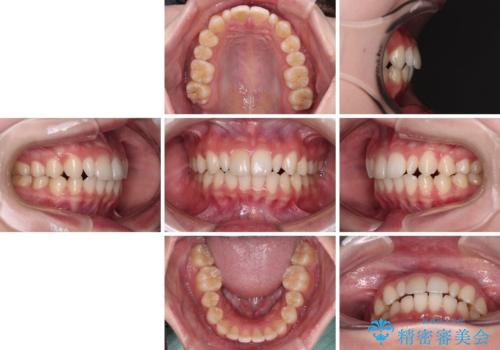

- 歯列のデコボコを気にして来院された患者様です。

安価に速やかに治療をしたいとのことで、メタルワイヤーにより矯正治療を行うこととしました。

上顎左右側切歯は矮小歯であり、矯正治療開始前にオールセラミッククラウンによる形態修正を兼ねた補綴治療を提案しましたが、特に気にならないとのことで、歯冠形態はそのままとしました。